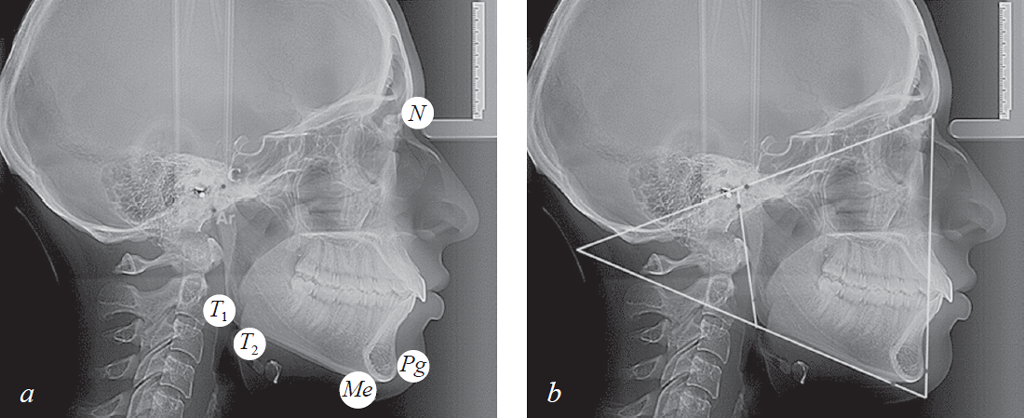

Во-первых, на телерентгенограмму наносили общепринятые точки: N, C, Ar, T1, T2, Pg.

Указанные точки служили ориентиром для проведения реперных линий (плоскостей), которые использовали в качестве ориентиров для сопоставления фрагментов томограмм с телерентгенограммой. В горизонтальном направлении проводили две линии. Верхняя линия, через точки N и С, отделяла лицевой отдел головы от краниального, и нами обозначалась как плоскость лицевого отдела головы или краниофасциальная линия (KFL).

Мандибулярная плоскость (МL) проходила через точки Gn и T2. Пересечение линий МL и KFL образовывало челюстно-лицевой угол, который может быть использован в качестве показателя типа роста лица (горизонтальный, вертикальный и нейтральный).

В вертикальном направлении соединяли точки N и Pg, полученную линию обозначали как «вертикальную линию лица». Касательная линия к ветви нижней челюсти (Ar – T1) с мандибулярной плоскостью образовывала угол нижней челюсти (рис. 1).

Рис. 1. Основные точки (a); линии используемые в качестве основных ориентиров для сопоставления рентгенограмм (b)

Fig. 1. Main points (a); lines used as the main reference points for the comparison of radiographs (b)

В-третьих, совмещали фрагменты.

При совмещении зубочелюстного резцового фрагмента томограммы точку Pg томограммы совмещали с аналогичной точкой телерентгенограммы, расположенной на передней вертикали лица (N – Pg). При этом условные срединные вертикали медиальных резцов, соединяющие режущие края с верхушками корней зубов, совпадали с межрезцовыми линиями.

При совмещении фрагмента височно-нижнечелюстного сустава точку С томограммы совмещали с одноименным ориентиром телерентгенограммы. При этом ориентировались на соответствие расположения точек Ar (рис. 3).

Рис. 3. Измерение гнатических углов (а); оценка положения сустава и резцов на совмещенных рентгенограммах (b)

Fig. 3. Measurement of gnatic angles (a); assessment of the position of the joint and incisors on combined radiographs (b)